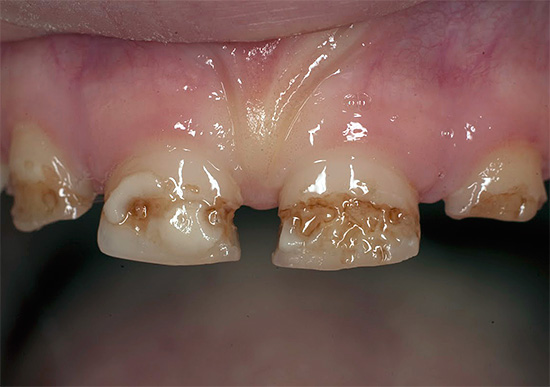

Oggi, a causa della popolarità della cura orale e della disponibilità di servizi dentali, la malattia è diventata meno comune, ma il problema è ancora rilevante nelle aree rurali e nei bambini in età scolare, quando quasi tutti i denti di un bambino sono affetti da carie (vedi l'esempio nella foto), e i genitori non sanno cosa fare in una situazione del genere.

Oltre al fatto che la carie è pericolosa per la salute, provoca dolore e limita la scelta del cibo, è anche un grave problema estetico. La foto sotto mostra un esempio di carie generalizzata: